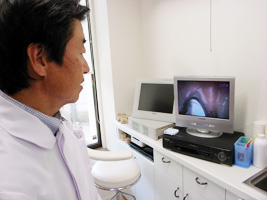

STEP4 検診

歯周病治療は毎回来院時に口腔内カメラを使って歯の裏側まで細部にわたってビデオ撮影し、歯磨きができているかチェックします。小さな歯石も見逃しません。